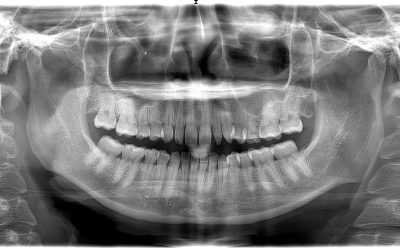

How CBCT Technology Changes How Dentists Plan Treatment

Dentists everywhere are dedicated to ensuring that they provide the most effective care for their patients possible. This is no mere case of altruism. In addition to producing results they can be proud of, patients return to dentists they trust with their oral health....